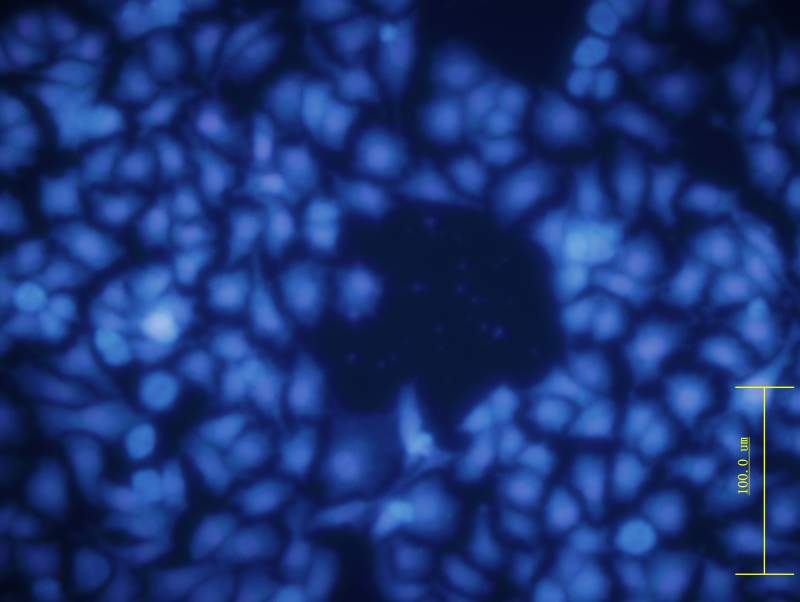

ϸ°û¾­¹ýÎïÀí½áºÏ»¯Ñ§ÁÆ·¨36 Сʱºó£¬ ÓÃhoechst Ⱦɫ ºÍPIȾɫ£¬¹Û²ìÆÚÐÎ̬¡£

45T-3.jpg

ÎïÀí»¯Ñ§ÁÆ·¨½áºÏ×÷ÓÃÓÚÖ×ÁöºóµÄHoechst ºÍPIȾɫ-5

48-3.jpg

ºìɫΪ»µËÀÂ𣿸ßÀ¶É«ÎªµòÍö£¿